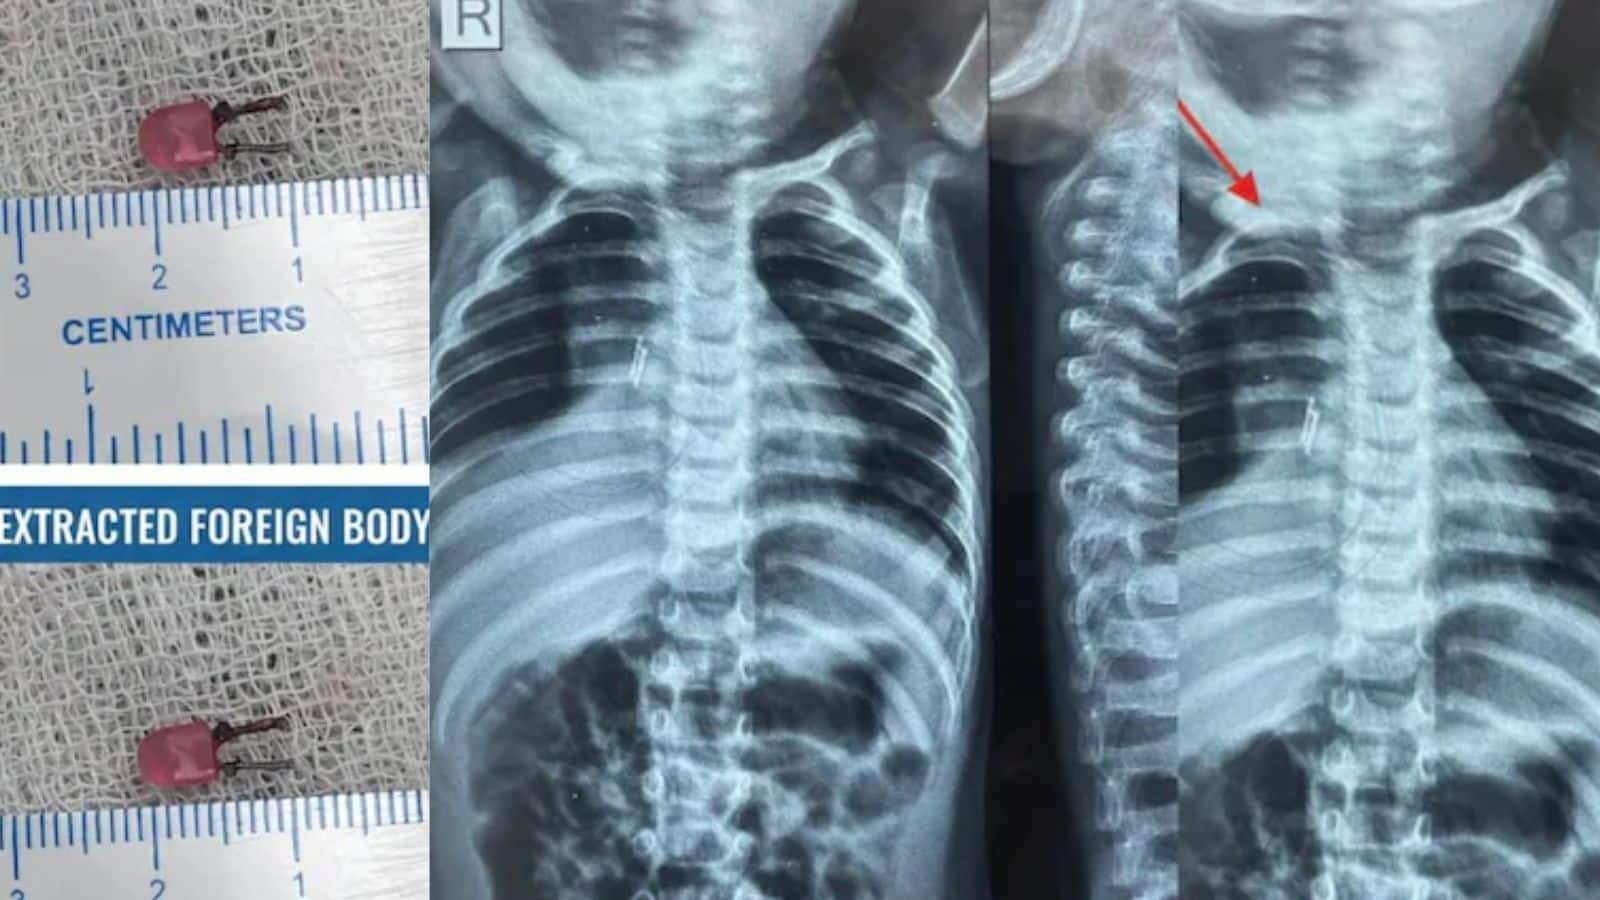

एक्स-रे करने पर पता चला कि बच्चे की सांस की नली (windpipe) में कोई अजनबी चीज फंसी हुई है। डॉक्टरों ने ब्रोंकोस्कोपी नाम की एक छोटी सर्जरी की। इसमें उन्होंने बच्चे की सांस की नली से एक छोटा LED बल्ब निकाला। यह बल्ब सिर्फ 1 सेंटीमीटर का था और बच्चे के मुंह से जाता हुआ गले में फंस गया था